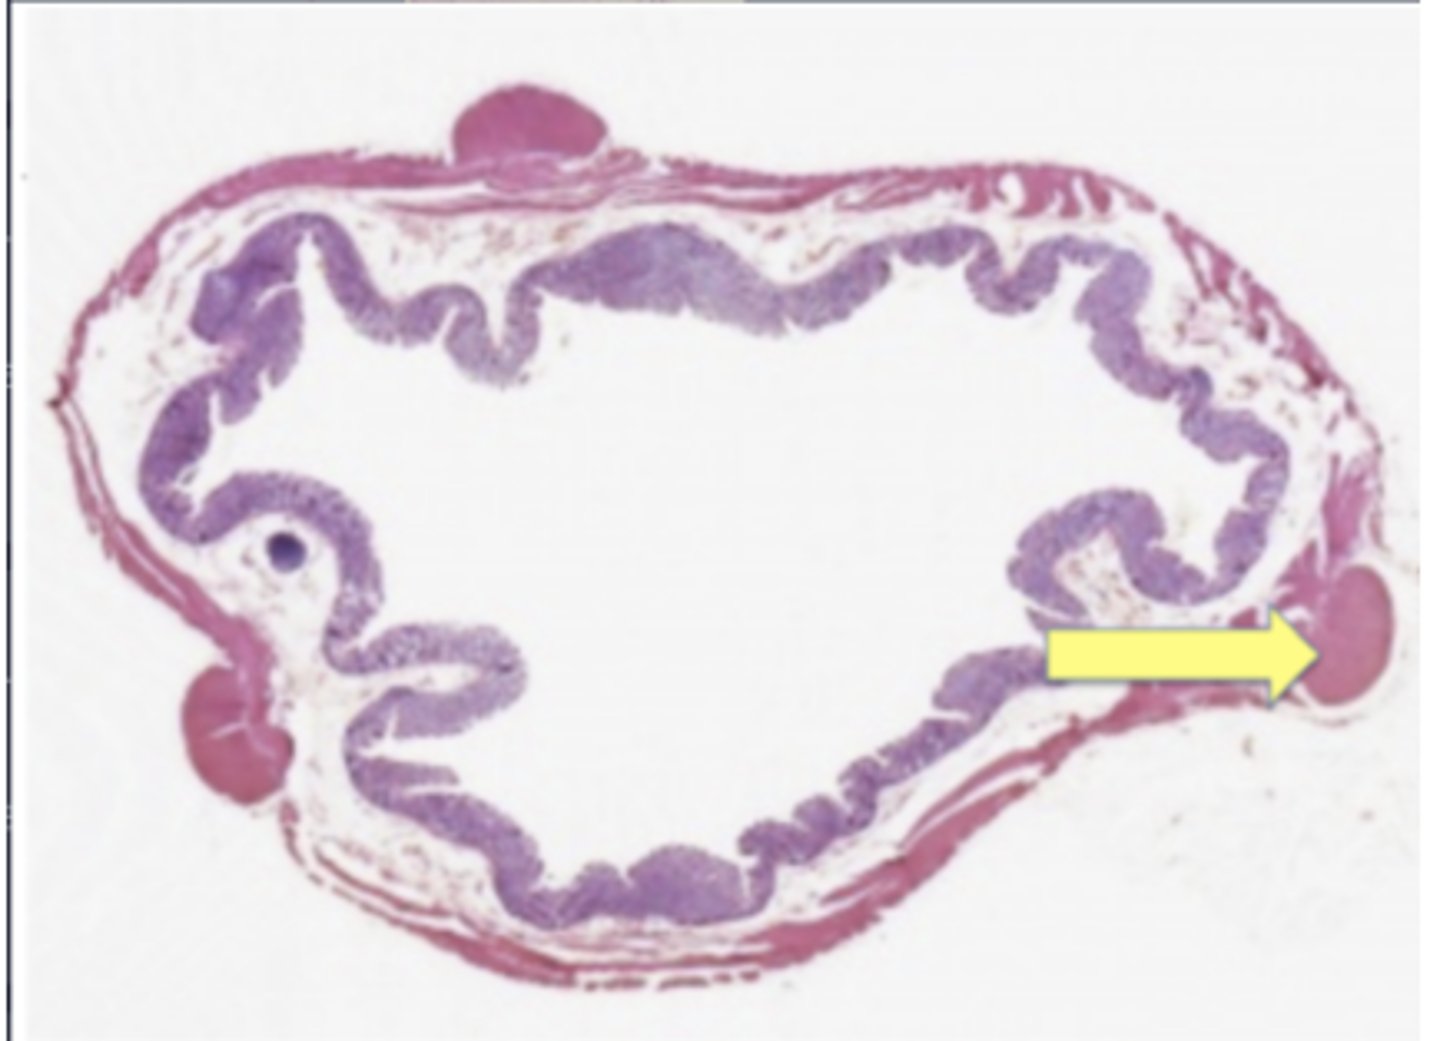

ureter

Bowman's capsule

thin loop of henle

cortical labyrinth

X - proximal convoluted tubule